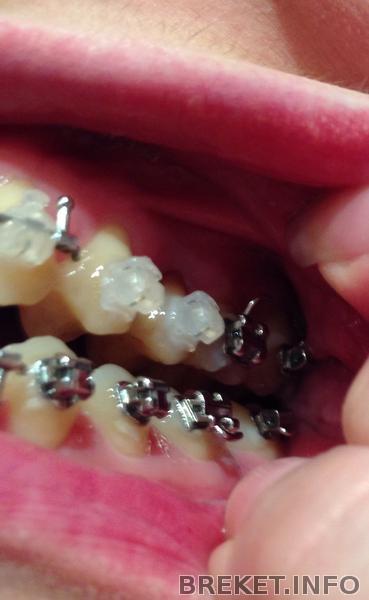

брекеты коронки на верхние единички

Ситуация "до", спустя неделю после установки, спустя два месяца после установки (плюс смена дуги). Прикус прямой.

Первая дуга в сравнении со второй прямоугольной вела себя гораздо "скромнее". Стою в магазине и думаю, что же я хочу съесть на ужин?